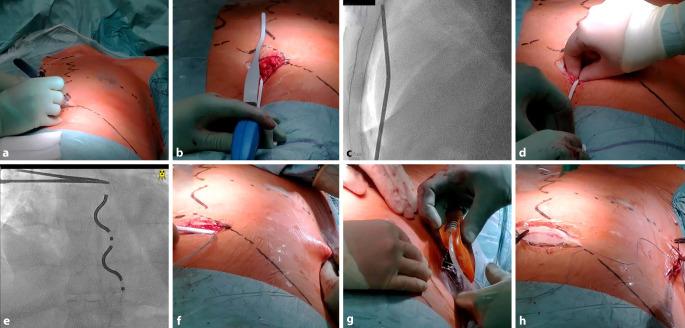

As an alternative to transvenous ICD systems, two non-transvenous ICD systems have been established in recent years: The subcutaneous ICD (S-ICD), which has been established for several years, has a presternal electrode that is implanted subcutaneously and offers a shock function and, to a limited extent, post-shock pacing. In addition, the extravascular ICD (EV-ICD) has been available in Europe since 2023 which does not require transvenous electrodes and offers the option of providing patients with antibradycardic and antitachycardic stimulation in combination with a conventional ICD function. The lead of this device is implanted substernally. Initial implantation results are promising in terms of safety and effectiveness. Both systems avoid possible complications of transvenous electrodes. This article provides practical guidance for the implantation technique and possible complications.

作为经静脉植入式心律转复除颤器(ICD)系统的替代方案,近年来已建立了两种非经静脉ICD系统:皮下ICD(S-ICD)已应用数年,其具有一个皮下植入的胸骨前电极,具备除颤功能,并在一定程度上具备电击后起搏功能。此外,血管外ICD(EV-ICD)自2023年起在欧洲上市,它不需要经静脉电极,并提供了结合传统ICD功能为患者提供抗心动过缓和抗心动过速刺激的选项。该设备的导线植入胸骨后。就安全性和有效性而言,初始植入结果很有前景。两种系统都避免了经静脉电极可能出现的并发症。本文为植入技术和可能出现的并发症提供了实用指南。